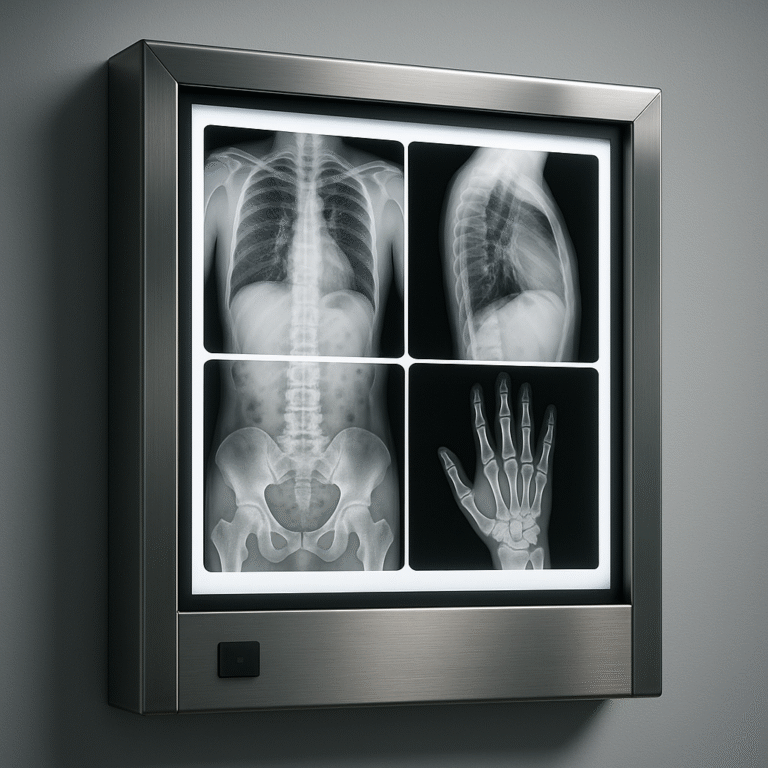

X RAY VIEWING SCREEN

X RAY VIEWING SCREEN

| Product | X-Ray Viewing Screen |

| Description |

X-ray reports are monitored when they are used with their viewing system. It is better to have the best X-ray viewing machines to gain the best results. Before X-ray technology came into existence, it was extremely tough to get to know any internal injuries of the body. X-ray imaging has numerous applications in the healthcare domain, but most importantly, X-rays help to monitor injuries related to bones, organs, tissues, and other internal body parts. X-rays use electromagnetic waves to produce images of internal organs. For studying the X-ray reports, a specific device To have the best viewing screens, choosing the right manufacturer is crucial. Our X-ray viewing screen creates a |